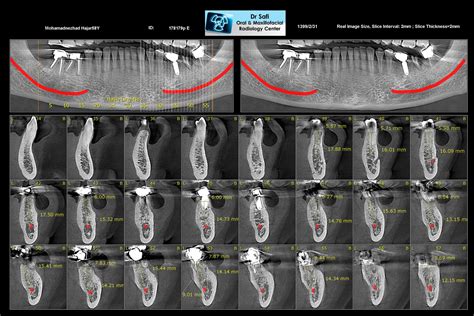

Cone Beam CT is a specialized type of X-ray imaging system used when regular dental or facial X-rays are not sufficient. The technology derives its name from the shape of the X-ray beam, which is emitted in a cone shape. During the scan, the machine rotates around the patient’s head, capturing hundreds of images from various angles in a single rotation. These images are then reconstructed by computer software into a highly detailed 3D model of the patient’s teeth, jawbone, soft tissues, nerve pathways, and nasal cavity.

- Endodontic Evaluation: It allows specialists to visualize hidden canals, root fractures, and periapical lesions that would be missed on standard periapical X-rays.

- Impacted Tooth Assessment: It is crucial for visualizing the exact position of impacted wisdom teeth and their relationship to the inferior alveolar nerve.

One of the most profound benefits is the diagnostic accuracy. Because the technology is not subject to the magnification or distortion inherent in 2D panoramic X-rays, measurements taken from a Cone Beam CT image are essentially 1:1 scale. This precision is vital for the success of complex surgeries, where millimeters can make the difference between a successful implant integration and nerve damage.